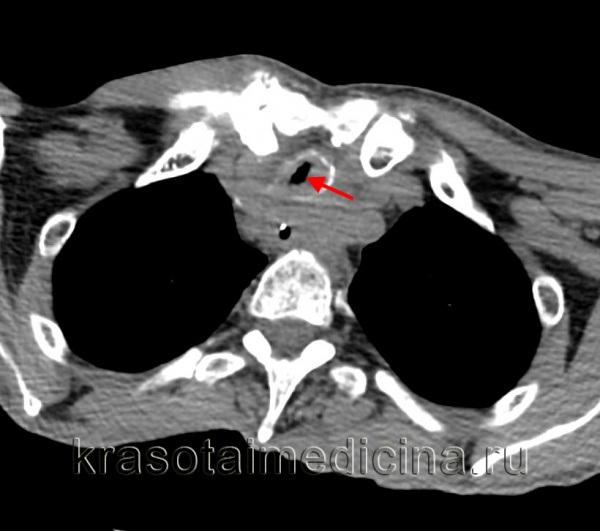

Клиническая диагностика трахеопищеводных свищей, как правило, не вызывает трудностей. Проявляются они приступообразным кашлем, который возникает во время приема пищи. Однако уточнение их локализации при рентгенологическом исследовании с барием и эзофагоскопии вызывает существенные трудности, особенно при небольших размерах свища. Более информативным оказывается трахеоскопия, при которой удается определить размеры свища, расстояние от голосовых связок и карины. Кроме того, значительную помощь в выявлении трахеопищеводных свищей оказывает также компьютерная томография.

![]() Рис.9. Компьютерная томограмма больного с трахеопищеводным свищом. | ![]() Рис. 10. Трахеоскопия больного с трахеопищеводным свищом, осложненным стенозом трахеи. |